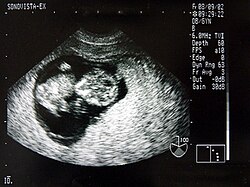

Ein wesentlicher Vorteil der Sonografie gegenüber dem in der Medizin ebenfalls häufig verwendeten Röntgen liegt in der Unschädlichkeit der eingesetzten Schallwellen. Auch sensible Gewebe wie bei Ungeborenen werden nicht beschädigt, die Untersuchung verläuft schmerzfrei.

Neben der Herztonwehenschreibung (Kardiotokografie) ist sie ein Standardverfahren in der Schwangerschaftsvorsorge. Eine spezielle Untersuchung der Pränataldiagnostik zur Erkennung von Entwicklungsstörungen und körperlichen Besonderheiten ist der Feinultraschall.

Das Ungeborene kann in der Gebärmutter nahezu komplett untersucht werden, da noch keinerlei Gasüberlagerung vorliegt und die Knochenbildung erst am Anfang steht:

- auch Lunge – Magen – Extremitätenknochen u. a.

Von den Monitorbildern werden zur Dokumentation Ausdrucke, sogenannte Sonogramme, oder gelegentlich Videoaufnahmen gemacht. Schwangeren wird häufig auch ein Bild ihres ungeborenen Kindes überlassen.